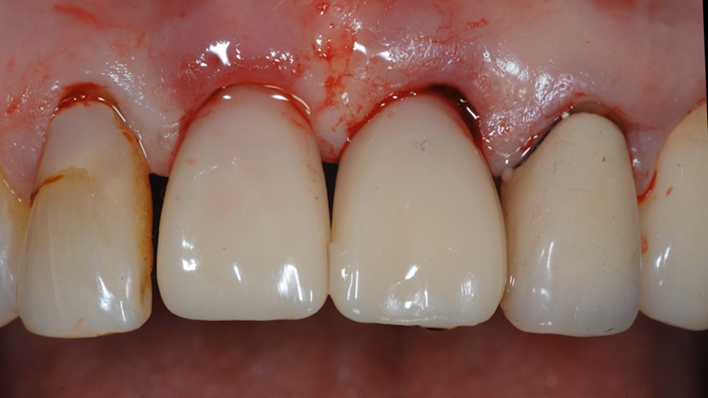

“ One implant /One tooth/ One hour step-by-step

+ associated connective graft ”

Clinical case: EImmediate implant placement & loading of #35 extraction socket with defect

- Courtesy of Dr. Kwang Bum Park, Korea -

Dr. Laurent Sers, immediate loading, digital guided surgery, digital ONE-DAY implant, maxillary anterior, #21, guided surgery, immediate loading, AnyRidge, R2GATE, Mega ISQ, R2GATE Full Surgical Kit

implant system, R2GATE Guide, R2GATE surgical kit (AnyRidge), Mega ISQ